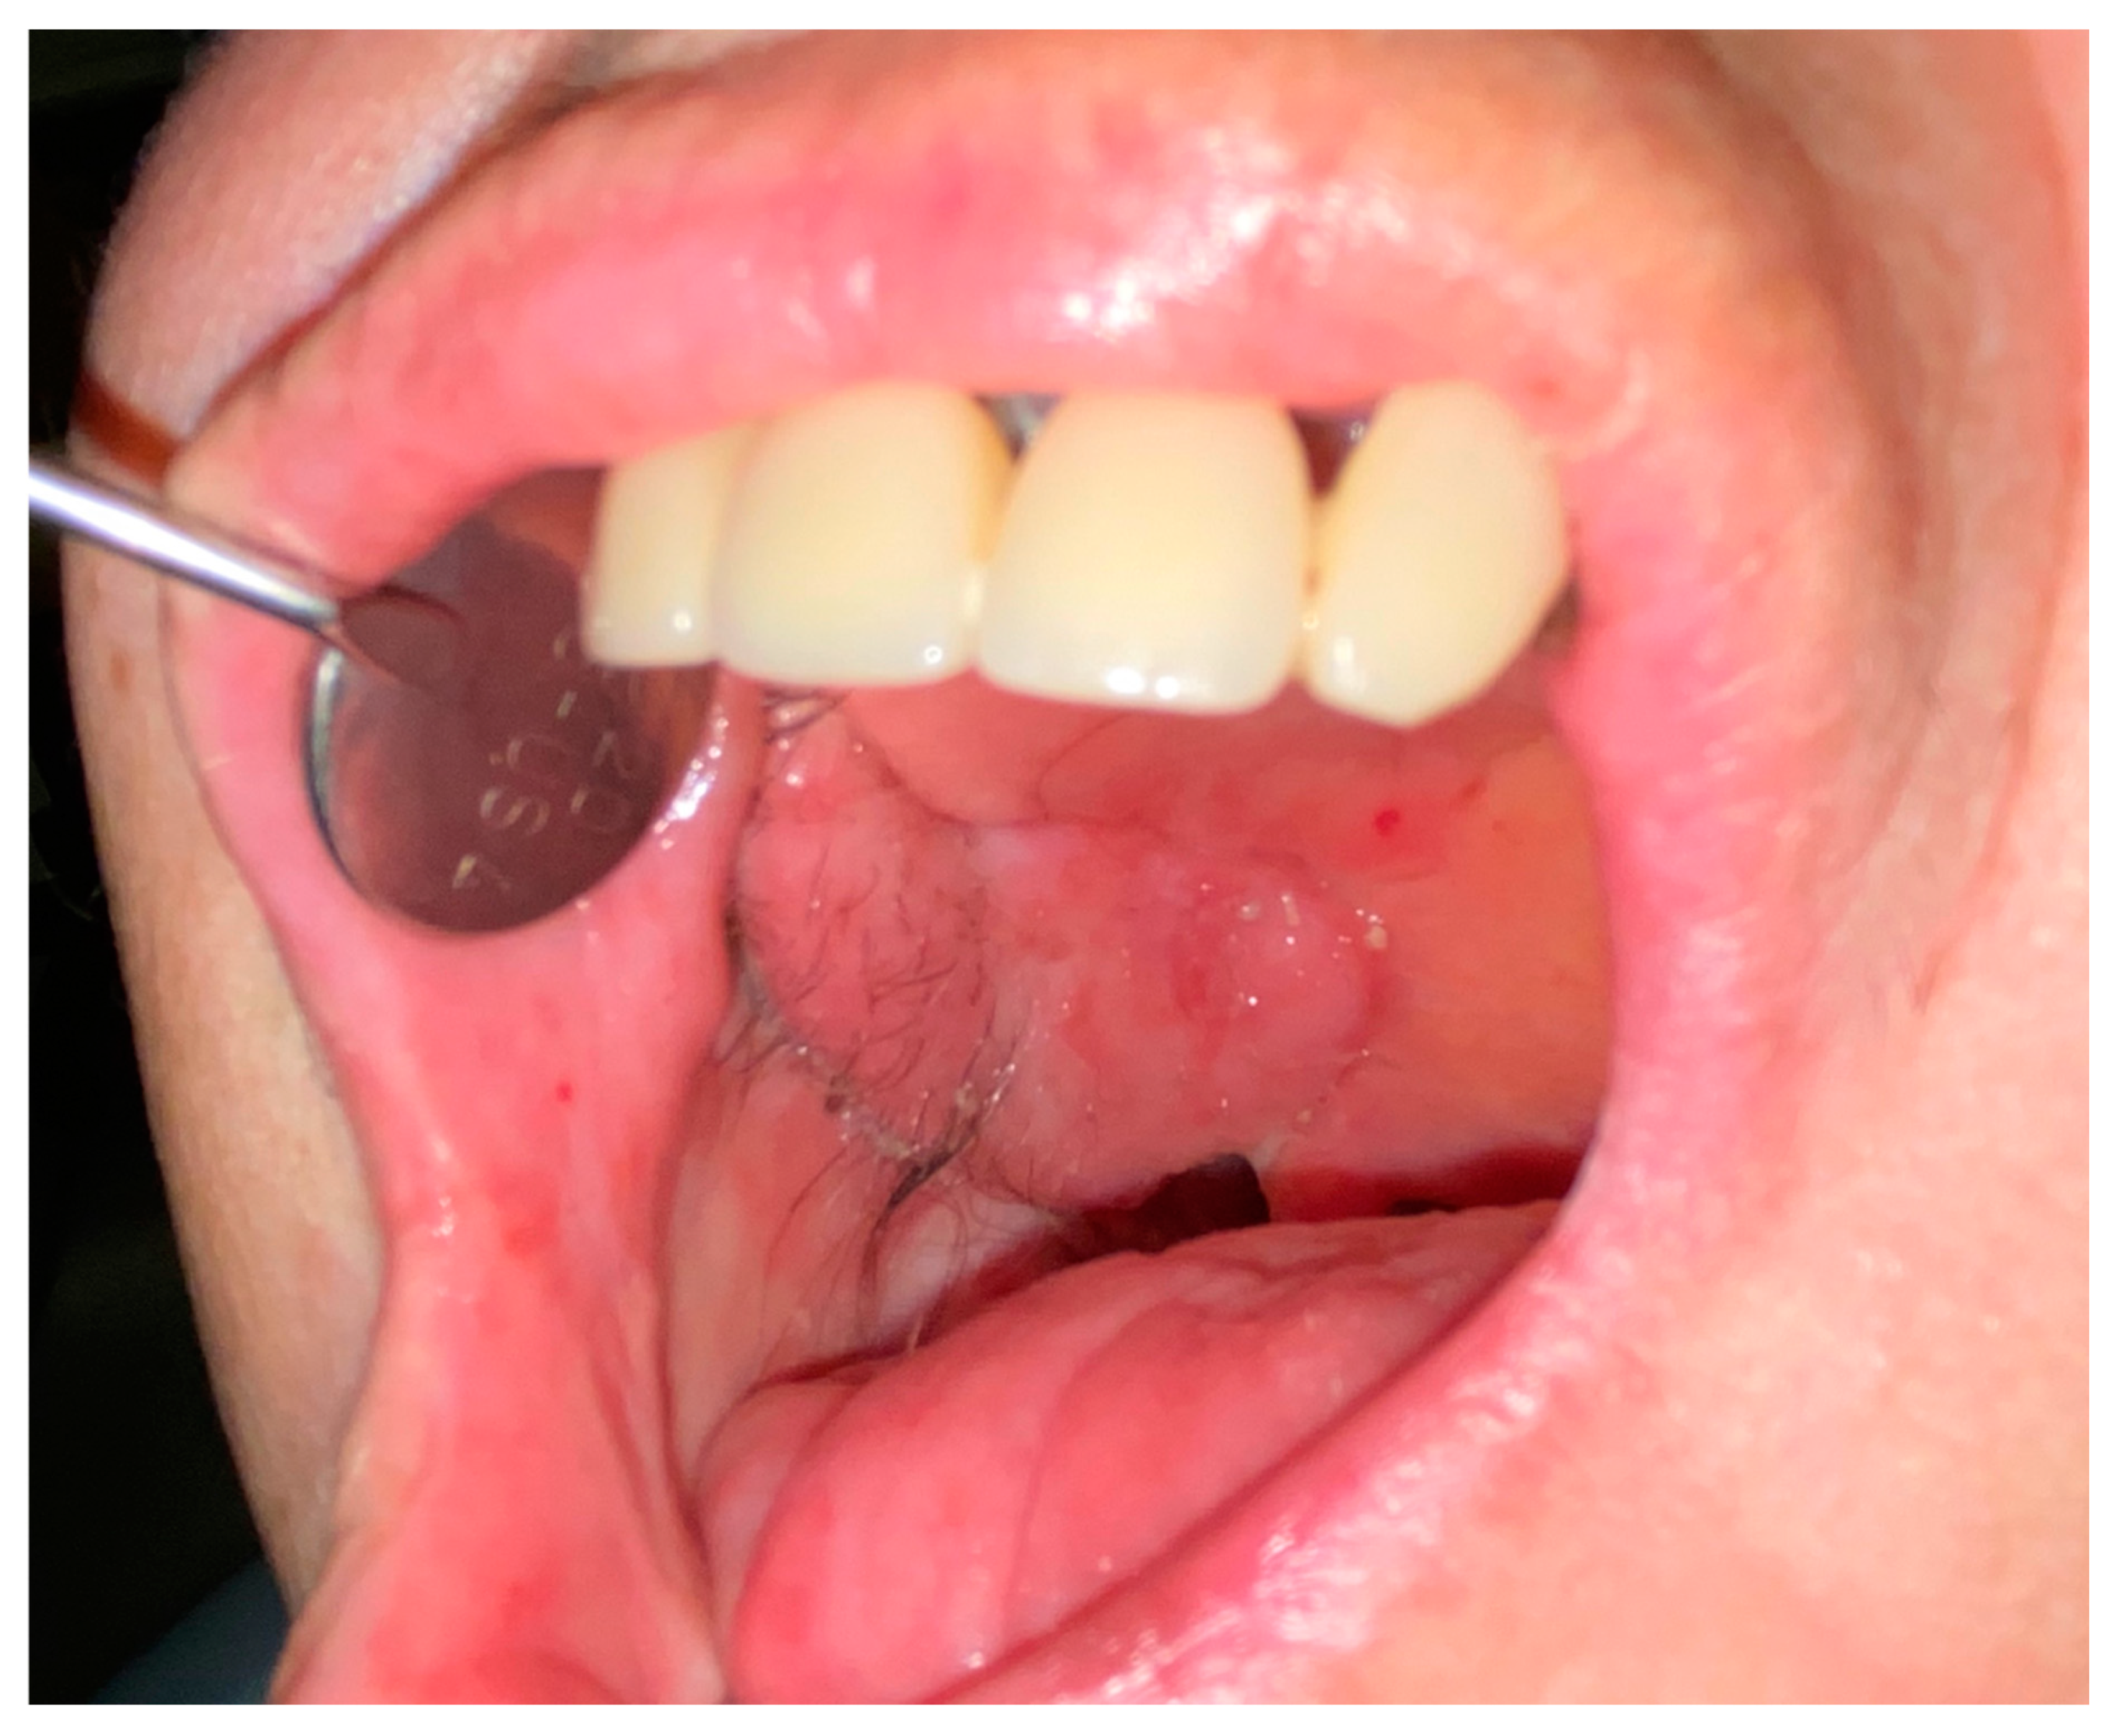

The average follow-up was nine months (range: 2–15 months). All of the reconstructions were successful and there were no major postoperative vascular complications. All flaps completely restored the oral cavity anatomy in terms of both tissue quality and quantity. No minor postoperative complications (e.g., partial flap loss caused by dehiscence/oroantral communication) were noted. Temporary paralysis of the frontal branch of the facial nerve was observed in one case. No postoperative functional issues at either the donor or recipient site were encountered; all patients healed well, as shown in Figure 9 and Figure 10.

Figure 9.

Reconstruction outcomes. Case 1. (A): The intraoral insert. (B): 2 weeks after surgery. (C): 3 months after surgery.

Figure 10.

Further reconstruction outcomes. Case 2 at 2 months after surgery. Right palate healing after composite skin/pericranium flap transfer.